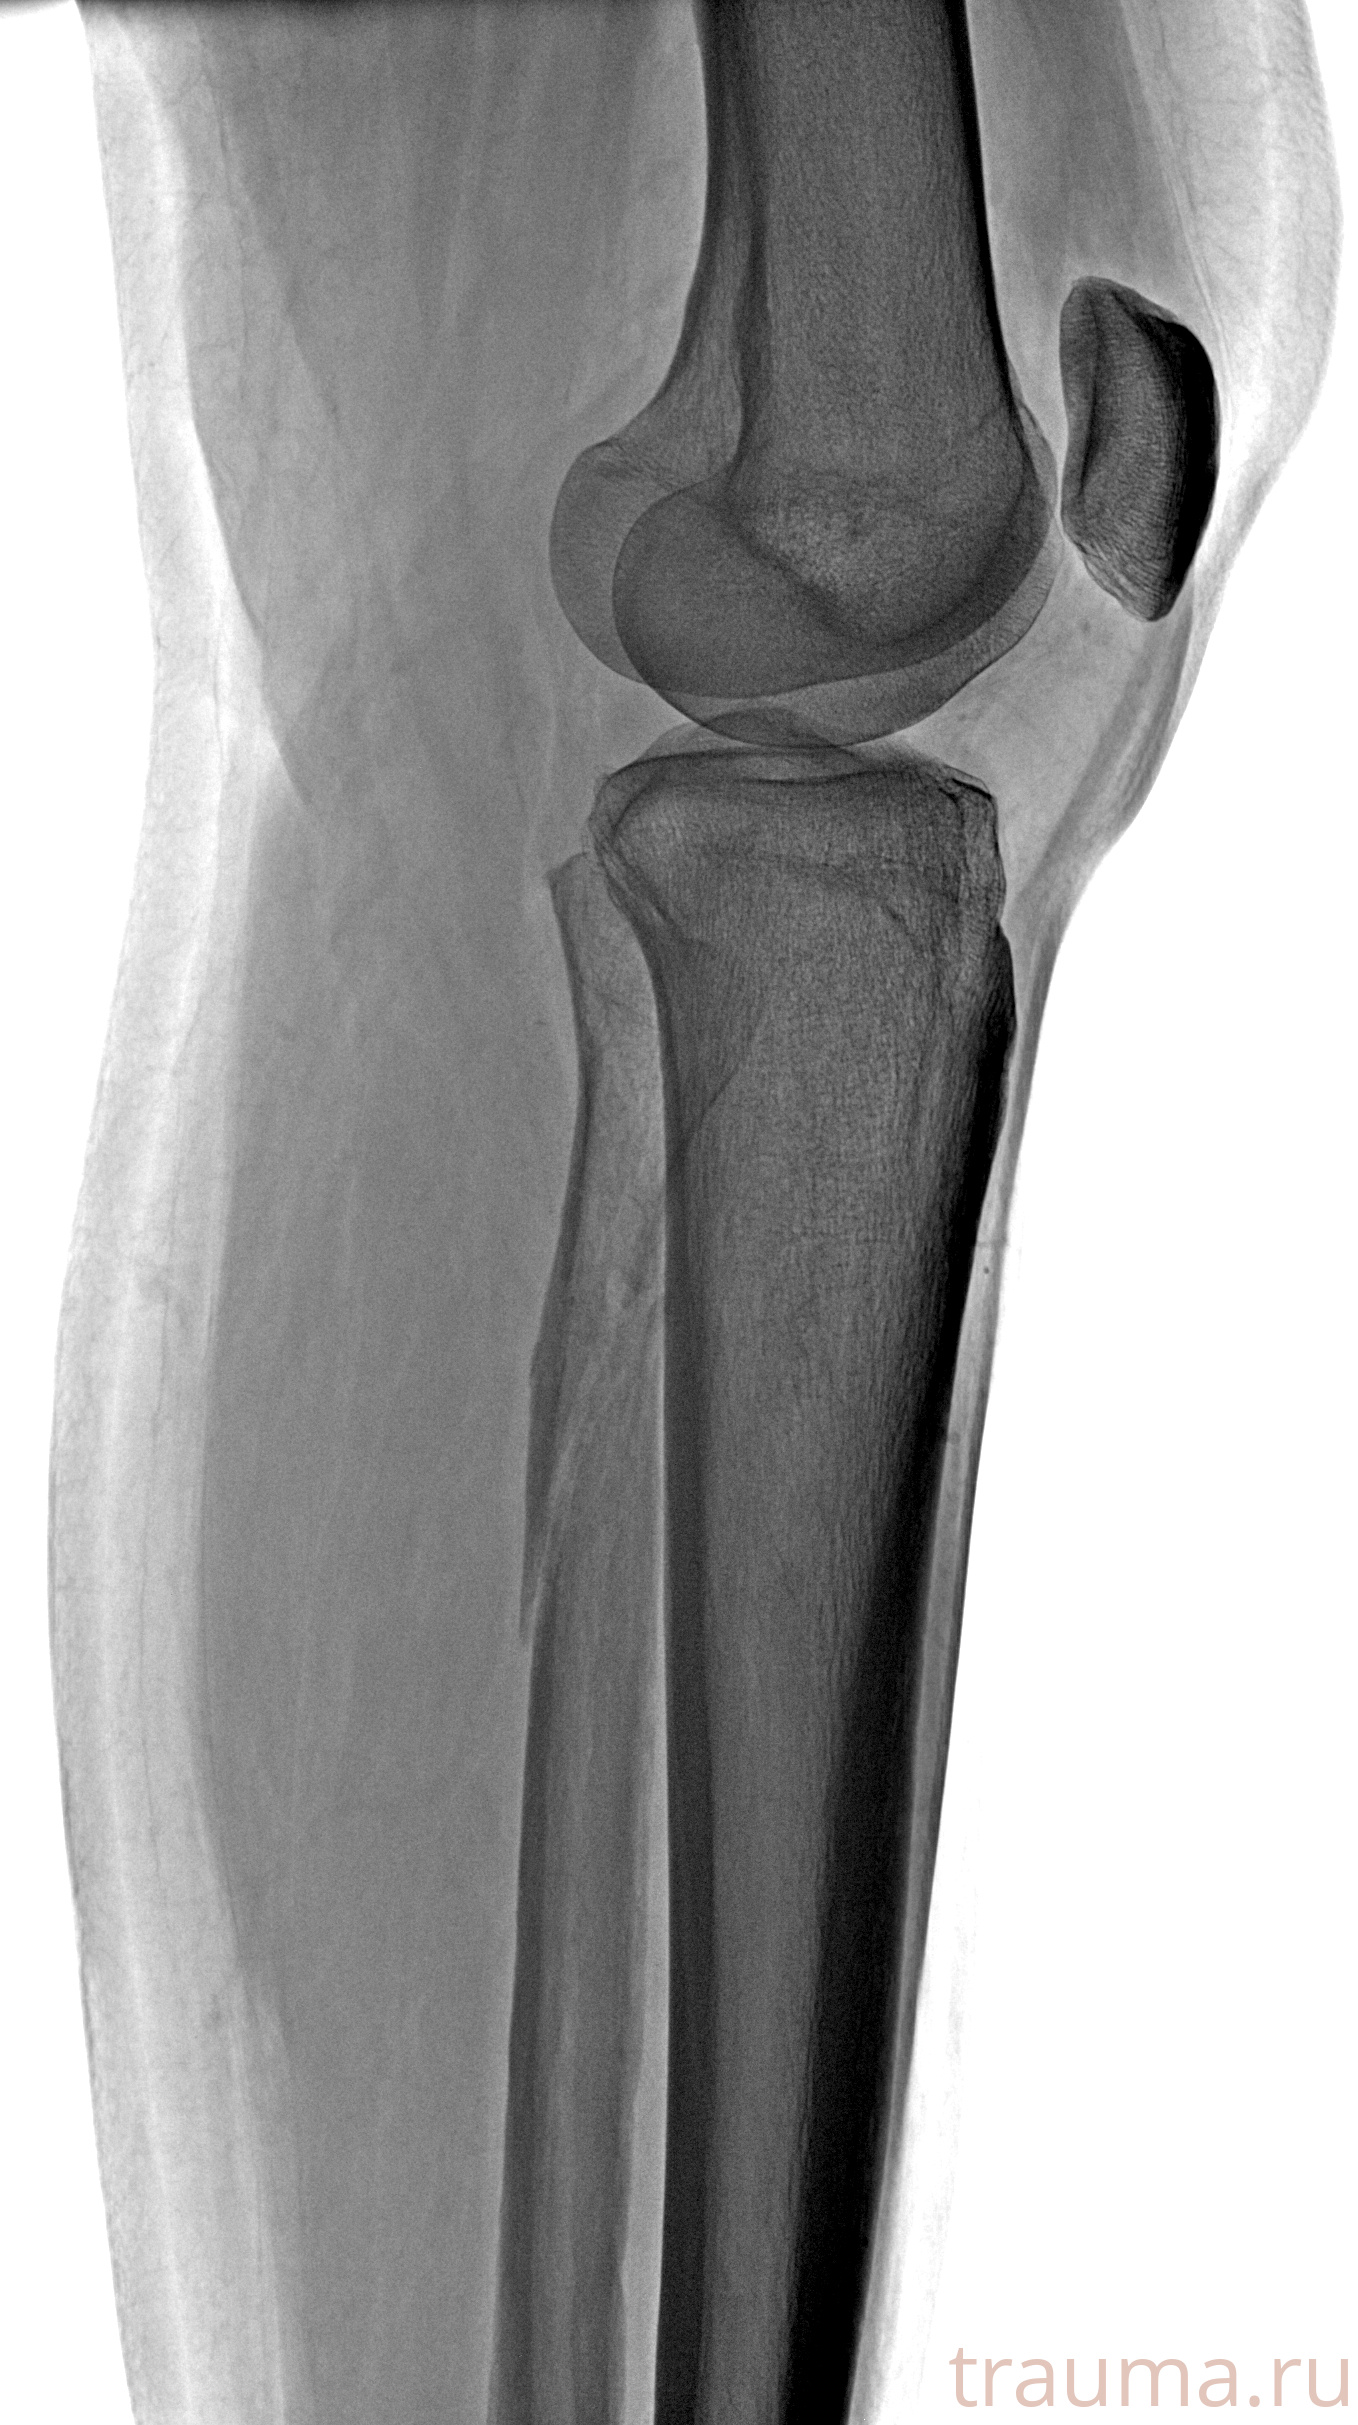

Рентген на дому: по вашему адресу приезжает врач-рентгенолог, травматолог-ортопед с мобильным рентгеновским аппаратом, проводит диагностику травмы или заболевания, делает необходимые рентгенограммы, дает рекомендации по дальнейшему лечению. Получить качественные снимки в домашних условиях возможно благодаря уникальной методике, разработанной МосРентген Центром для института  Склифосовского